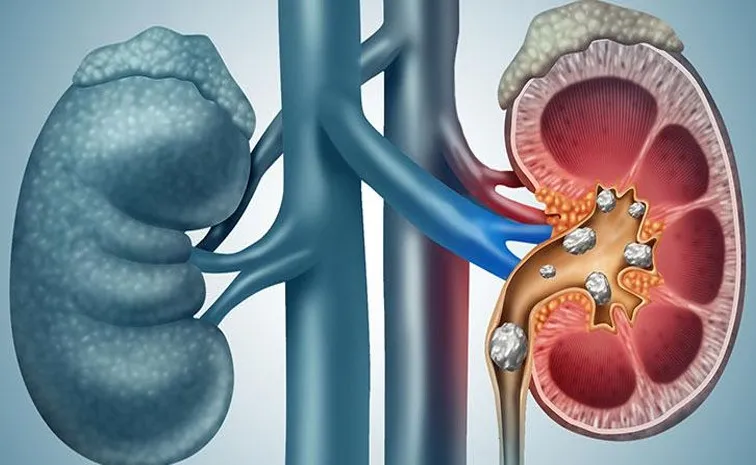

తెలంగాణలో 2.5 రెట్లు పెరిగిన కిడ్నీ రాళ్ల కేసులు

హైదరాబాద్ తెలంగాణలో వేసవి ముదురుతోంది. ఎండలు ఠారెత్తిస్తున్నాయి. అదే సమయంలో రాష్ట్రవ్యాప్తంగా ఈ సీజన్ల కిడ్నీలలో రాళ్లు ఏర్పడే కేసులు రెండు నుంచి రెండున్నర రెట్లు పెరిగాయని ఏషియన్ ఇన్స్టిట్యూట్ ఆఫ్ నెఫ్రాలజీ అండ్ యూరాలజీ (ఏఐఎన్యూ) తన నివేదికలో తెలిపింది. డీహైడ్రేషన్, ఆహారపు అలవాట్లు సరిగా లేకపోవడం, విపరీతంగా ఎండల్లో తిరగడం వల్ల రోజుకు సుమారు 300 నుంచి 400 మంది రోగులు కిడ్నీలో రాళ్ల సమస్యతో రావడంతో వారికి ఏఐఎన్యూల చికిత్సలు చేస్తున్నారు. వేసవి అంటేనే “స్టోన్ సీజన్” అంటారు. ఈ కాలంలో ముఖ్యంగా కిడ్నీలకు చాలా ప్రమాదం ఉంటుంది. ప్రధానంగా శరీరంలో నీరు ఆవిరి అయిపోవడం, ఉప్పు ఎక్కువగా తినడం, తగినంత నీరు తీసుకోకపోవడం వంటి కారణాల వల్ల వేసవిలో కిడ్నీలలో రాళ్లు ఎక్కువగా ఏర్పడతాయి.

రోజుకు సగటున 300 నుంచి 400 వరకు కిడ్నీలో రాళ్ల కేసులు వస్తున్నాయి. ఇటీవలి కాలంలో ఇది బాగా ఎక్కువ.

రాష్ట్ర వ్యాప్తంగా శీతాకాలంతో పోలిస్తే ఈ బాధితుల సంఖ్య రెట్టింపు దాటిపోయింది.

జంక్ ఫుడ్ తినడం, ఎక్కువగా కదలకపోవడం, తగినంత నీరు తాగకపోవడంతో పిల్లలు, యువతలో ఈ సమస్య ఎక్కువవుతోంది.

10-17 సంవత్సరాల మధ్య పిల్లల్ల రాళ్లు ఎక్కువగా కనిపిస్తున్నాయి. పాఠశాలలో ఉన్నప్పుడు నీళ్లు తాగకపోవడం, స్నాక్స్ ప్యాకెట్లు కొని తినడం, కూల్ డ్రింకులు తాగడం దీనికి కారణం.

పురుషులతో పోలిస్తే మహిళలకు ఈ సమస్య కొంత తక్కువే (సుమారు 40% తక్కువ). కానీ, గర్బవతులుగా ఉన్నప్పుడు ఈ సమస్య వచ్చి, గుర్తించకపోతే ముప్పు ఎక్కువ.

పిల్లల్లో ఈ సమస్య వల్ల దీర్ఘకాలంలో వారి కిడ్నీల ఆరోగ్యంపై ప్రభావం పడుతుంది.

ఈ సందర్భంగా ఏఐఎన్యూకు చెందిన సీనియర్ కన్సల్టెంట్ యూరాలజిస్ట్ డాక్టర్ తైఫ్ బెండెగెరి మాట్లాడుతూ, “కిడ్నీలో రాళ్ల కేసులు ఈసారి అసాధారణంగా పెరిగాయి. ముఖ్యంగా పిల్లలు, యువతలో ఈ సమస్య ఎక్కువగా కనిపిస్తోంది. వేడి పెరిగిపోవడం, తగినంత నీరు తాగకపోవడం ఇందుకు ప్రధాన కారణాలు. పాఠశాలకు వెళ్లే పిల్లలు జంక్ ఫుడ్ ఎక్కువగా తినడం వల్ల వారికి ఈ కిడ్నీలో రాళ్ల సమస్య ఎక్కువ అవడం ఆందోళన కలిగిస్తోంది. ఈ రాళ్ల సమస్య కేవలం పెద్దవాళ్లది అనుకోకూడదు. పిల్లల తల్లిదండ్రులతో పాటు పాఠశాలలు కూడా దీనిపై అవగాహన పొందాలి. తగినంత నీళ్లు తాగడం, సరైన ఆహారం తీసుకోవడం, సమస్యను త్వరగా గుర్తించడం వల్ల చాలా తేడా ఉంటుంది. ముఖ్యంగా.. వేసవి నెలల్ల ఈ జాగ్రత్తలు తప్పక తీసుకోవాలి” అని సూచించారు.